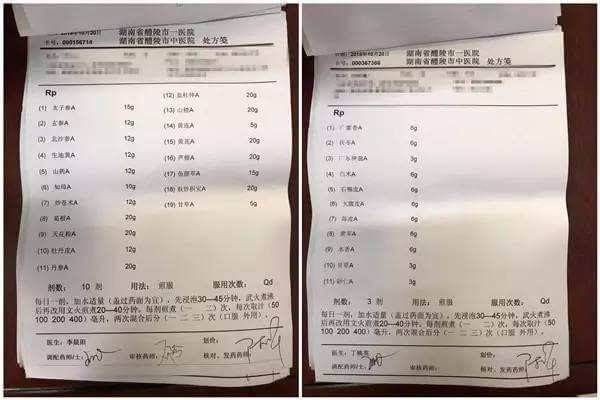

后来,还是朋友在微信上推荐了一张微信名片给我,是一位非常传奇的老中医,说他是中国的肾派泰斗,三百多年王氏中医当代传承人之一,专治男人肾虚早泄,增大增粗补睾有绝活。我将自己的情况详细告知了老中医,他了解了我阳痿早泄的具体情况后,诊断我是睾丸酮分泌不足,海绵体发育不良,所以用传统的方法补肾毫无作用。病情诊断结束,老中医给我开了2个月的祖传单子让我调理,我当时也没抱太大希望,但想到已经受了那么多苦了,死马当活马医,靠着老中医给的单子调理!

王剑峰院长对于药材的把握更是严格,精选的材料就像好马遇到伯乐一样难,药材好,药才好!为了保证药材品质,院长对药材的产地、年份、炮制都非常严格,为了得到道地药材,他每年都会去药材原产地,直接从药农们手里收购。

王剑峰院长面对心存疑虑的男性患者,在远程诊断以后,都让学生们做了详细的登记,连夜研究他们的调理方案!语重心长细说一番:"人的体质千差万别,合适的才是重要的,只要对路,药材选好、炮制到位,效果就会快,我既然对自己有信心,就敢先给他们诊断开方,方子清清楚楚,明明白白?让每一位患者都能放心,安心治疗""我就是要打破这种体质的牢笼,砸那些不钻研医术,只想先捞捞了钱,再胡乱应付患者的人"